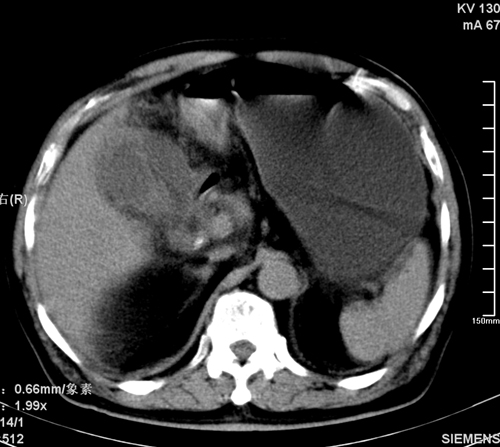

以下是引用liaoqiang在2008-3-27 15:57:00的发言:[br]1右肾脏周多发大小不一球形影,考虑肾脏囊肿可能性大。2胆囊边界欠清楚。考虑胆囊炎可能性。

以下是引用随光逐影在2008-3-27 16:33:00的发言:[br]考虑为:1)双肾囊肿可能。2)急性胆囊炎。建议:行进一步检查。